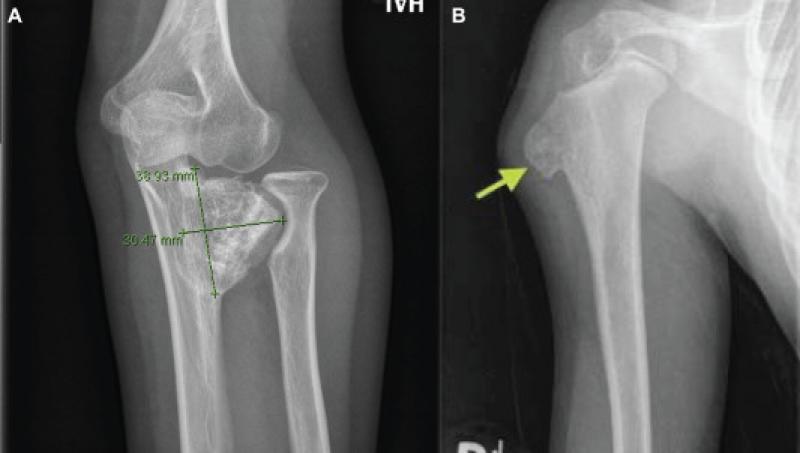

The Osteochondromas Treatment market is also influenced by advancements in medical imaging technology and surgical techniques. High-resolution imaging modalities, such as MRI and CT scans, enable accurate diagnosis and assessment of osteochondromas, aiding in treatment planning. Additionally, minimally invasive surgical approaches, including arthroscopic resection, are becoming more widely adopted due to their potential for reduced postoperative pain and quicker recovery times. These innovations are enhancing the overall patient experience and expanding the market for osteochondromas treatment options.